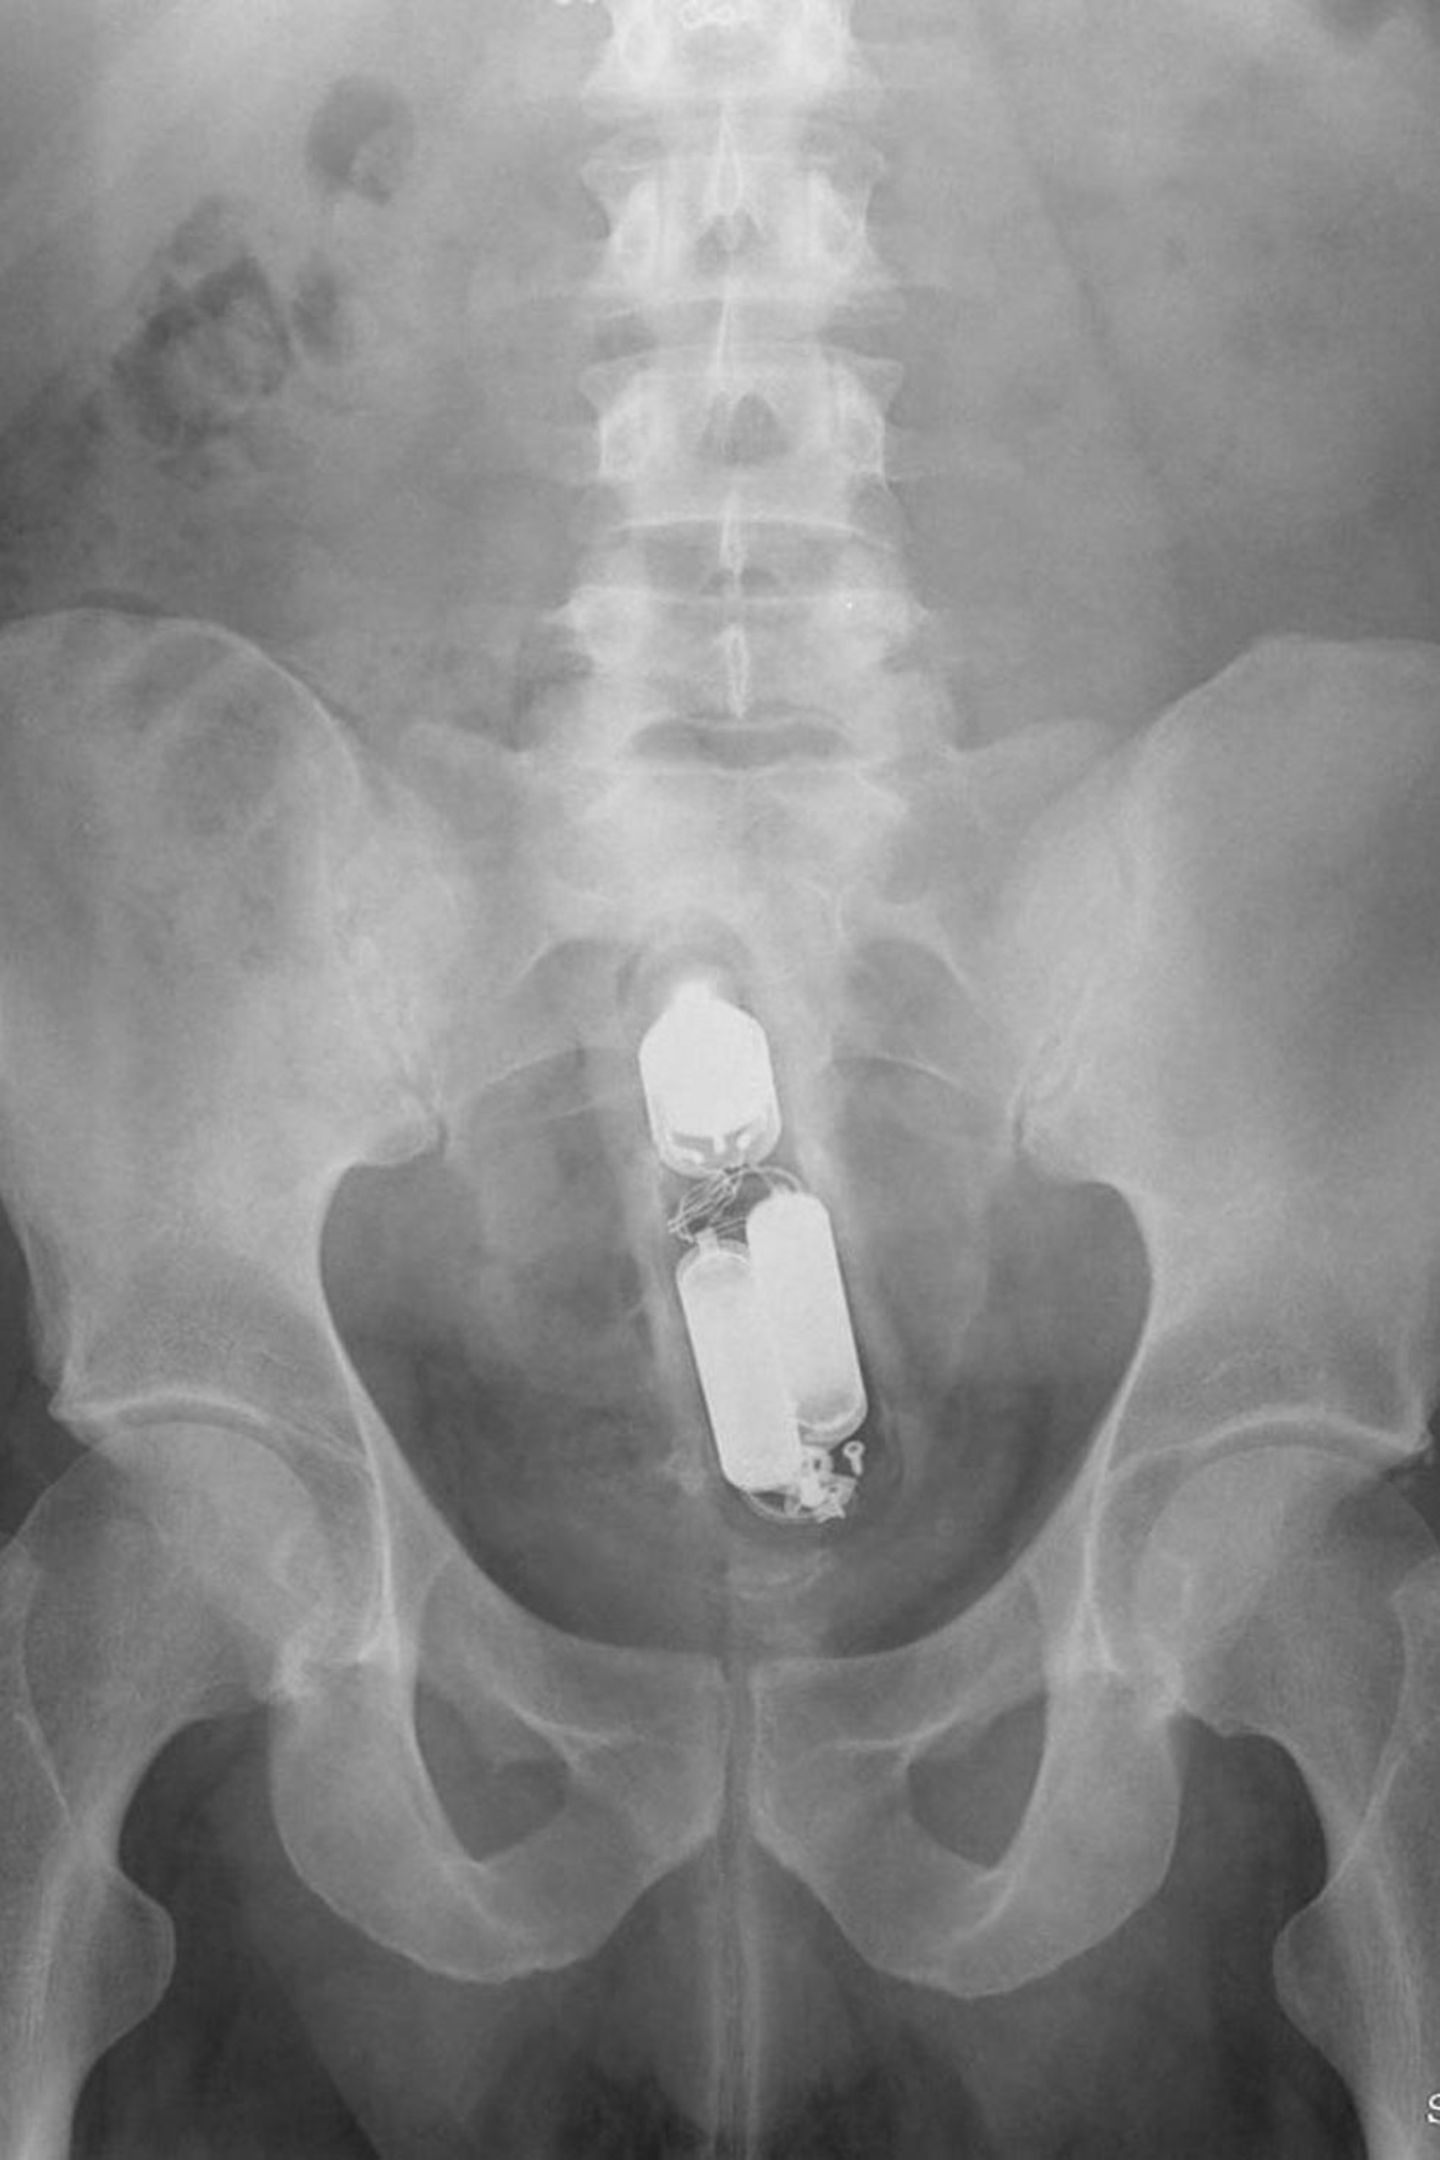

• Vom Dildo bis zur Orange: Was Ärzte auf Röntgenbildern entdecken

An den Batterien zu erkennen: ein Vibrator